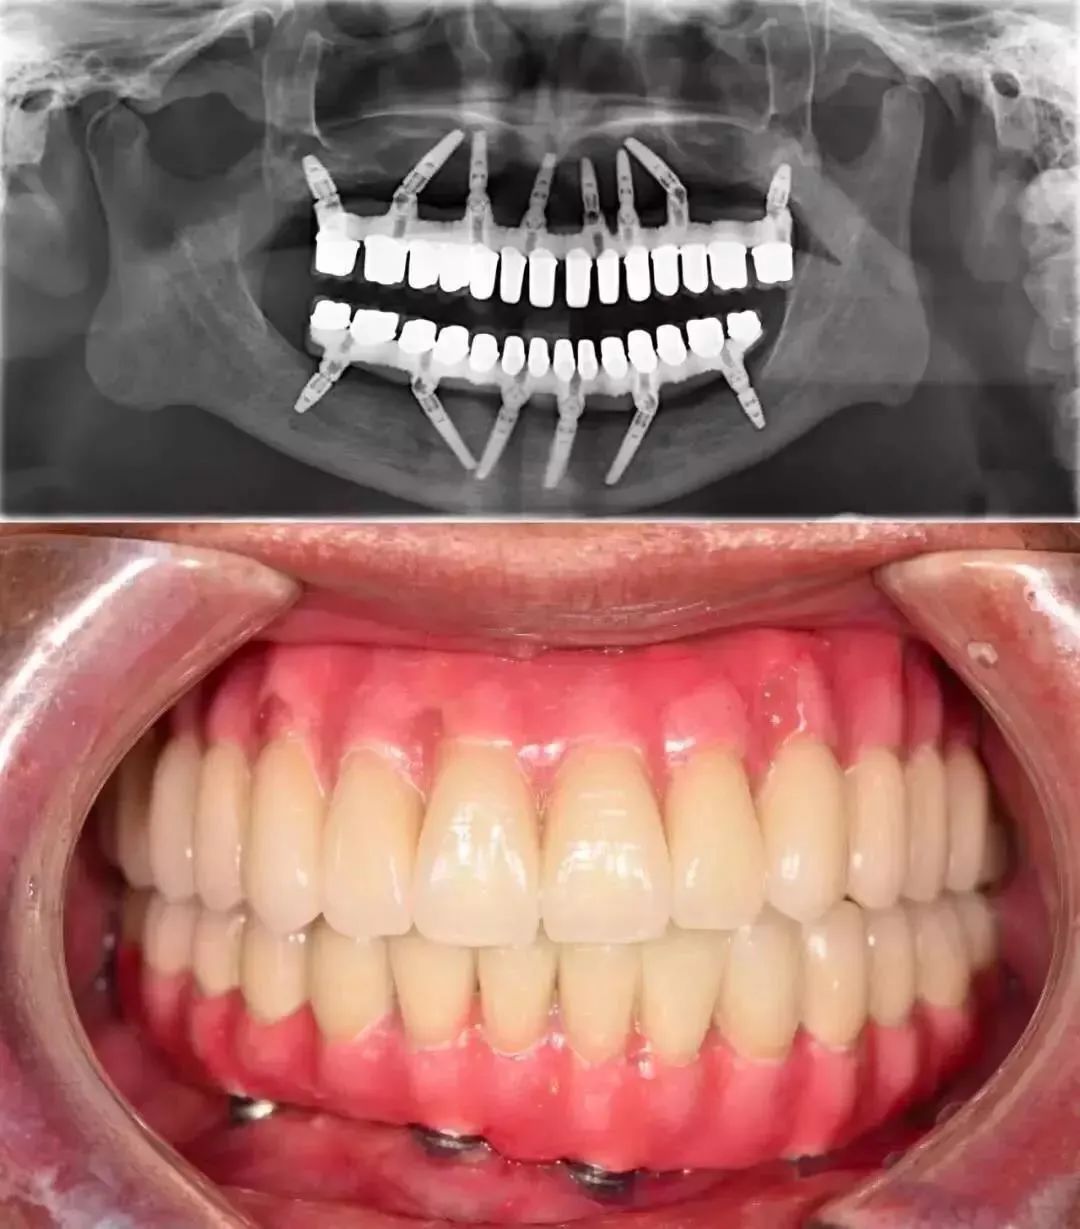

价格高昂种植义齿 图片来源:@种牙匠黄建生

牙周炎的诊断一旦确立,即预示着漫长而繁琐的治疗,这比早期单纯的牙龈炎治疗要复杂得多。

不仅花费不在一个档次,同时涉及到个人长期口腔卫生管理与维护水平的差异,疗效也因人而异。